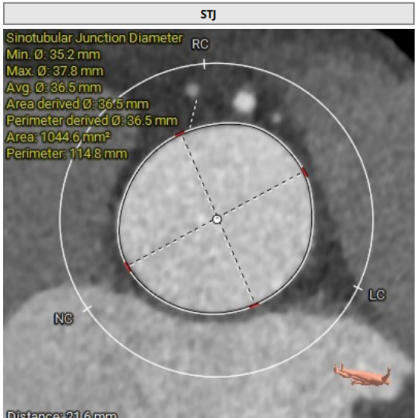

● 瓦氏窦、窦管交界内径正常,升主动脉扩张;

主动脉根部测量

瓣上结构测量